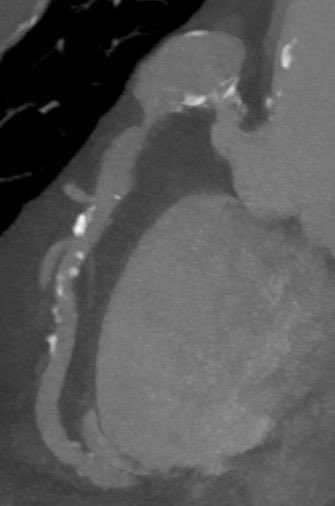

Postaneurysmal high-grade stenosis of the right coronary artery in the cardiac CT with the corresponding findings of the coronary angiography before and after stenting. What a beautiful case! @Steph_Achenbach @M_Marwan_ @monique_trobs @escardio @Heart_SCCT

0

2

5